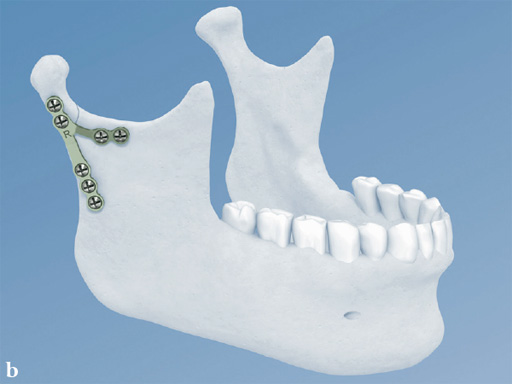

Lambda Plate

The lambda plate comes in a left and right version. It emulates a two-plate technique as its specific shape and 7-hole design with the width of a single plate at the top segment allows the surgeon to advance the lambda plate high up into the very narrow zone of the condylar neck just below the head. The fixation arms straddle the mandibular canal to avoid injury risk of the inferior alveolar nerve.

The lambda plate can be placed using retromandibular or submandibular surgical approaches. For positioning, the straight 5-hole segment is placed parallel to the posterior ramus border aligned with the condylar head. If required the anterior arm may be bent to fit the bony surface below the sigmoid notch.

Both plates are based on the matrix mandible system platform. Therefore, they are compatible with the existing matrix instrumentation and use the established color-coding for easy identification in the operating room. Both are 1.0 mm thick and malleable (green-grey color coding) and manufactured from commercially pure titanium.